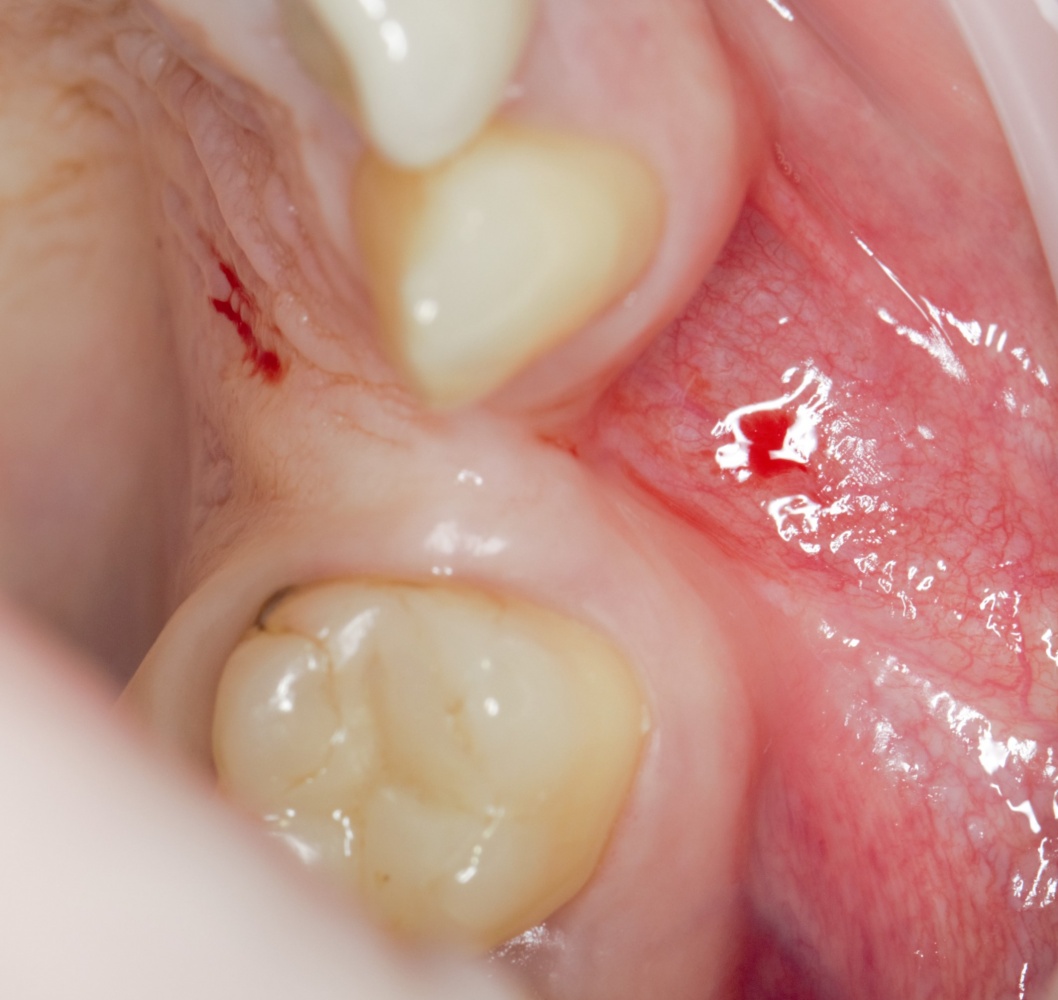

Конечно, она есть. Тот же принцип медицинской целесообразности и бритва Оккама поясняют нам, почему на верхней челюсти АТККФ используется реже, а при синуслифтинге не используется вообще — за очень-очень редким исключением:

Просто такие операции получаются сложнее: нужен донорский участок (верхней челюсти таковых не так много), из-за этого нарушается «принцип одной раны» (основная операция и забор аутографта проводятся через один разрез).

При синуслифтинге мы, в любом случае, используем ТОЛЬКО биоматериалы — так, что дополнительная остеопластика, по сути, ничего не меняет — себестоимость вмешательства остаётся, практически, такой же. Следовательно, есть ли смысл при небольших дефектах заморачиваться и усложнять операцию? Конечно, смысла нет.